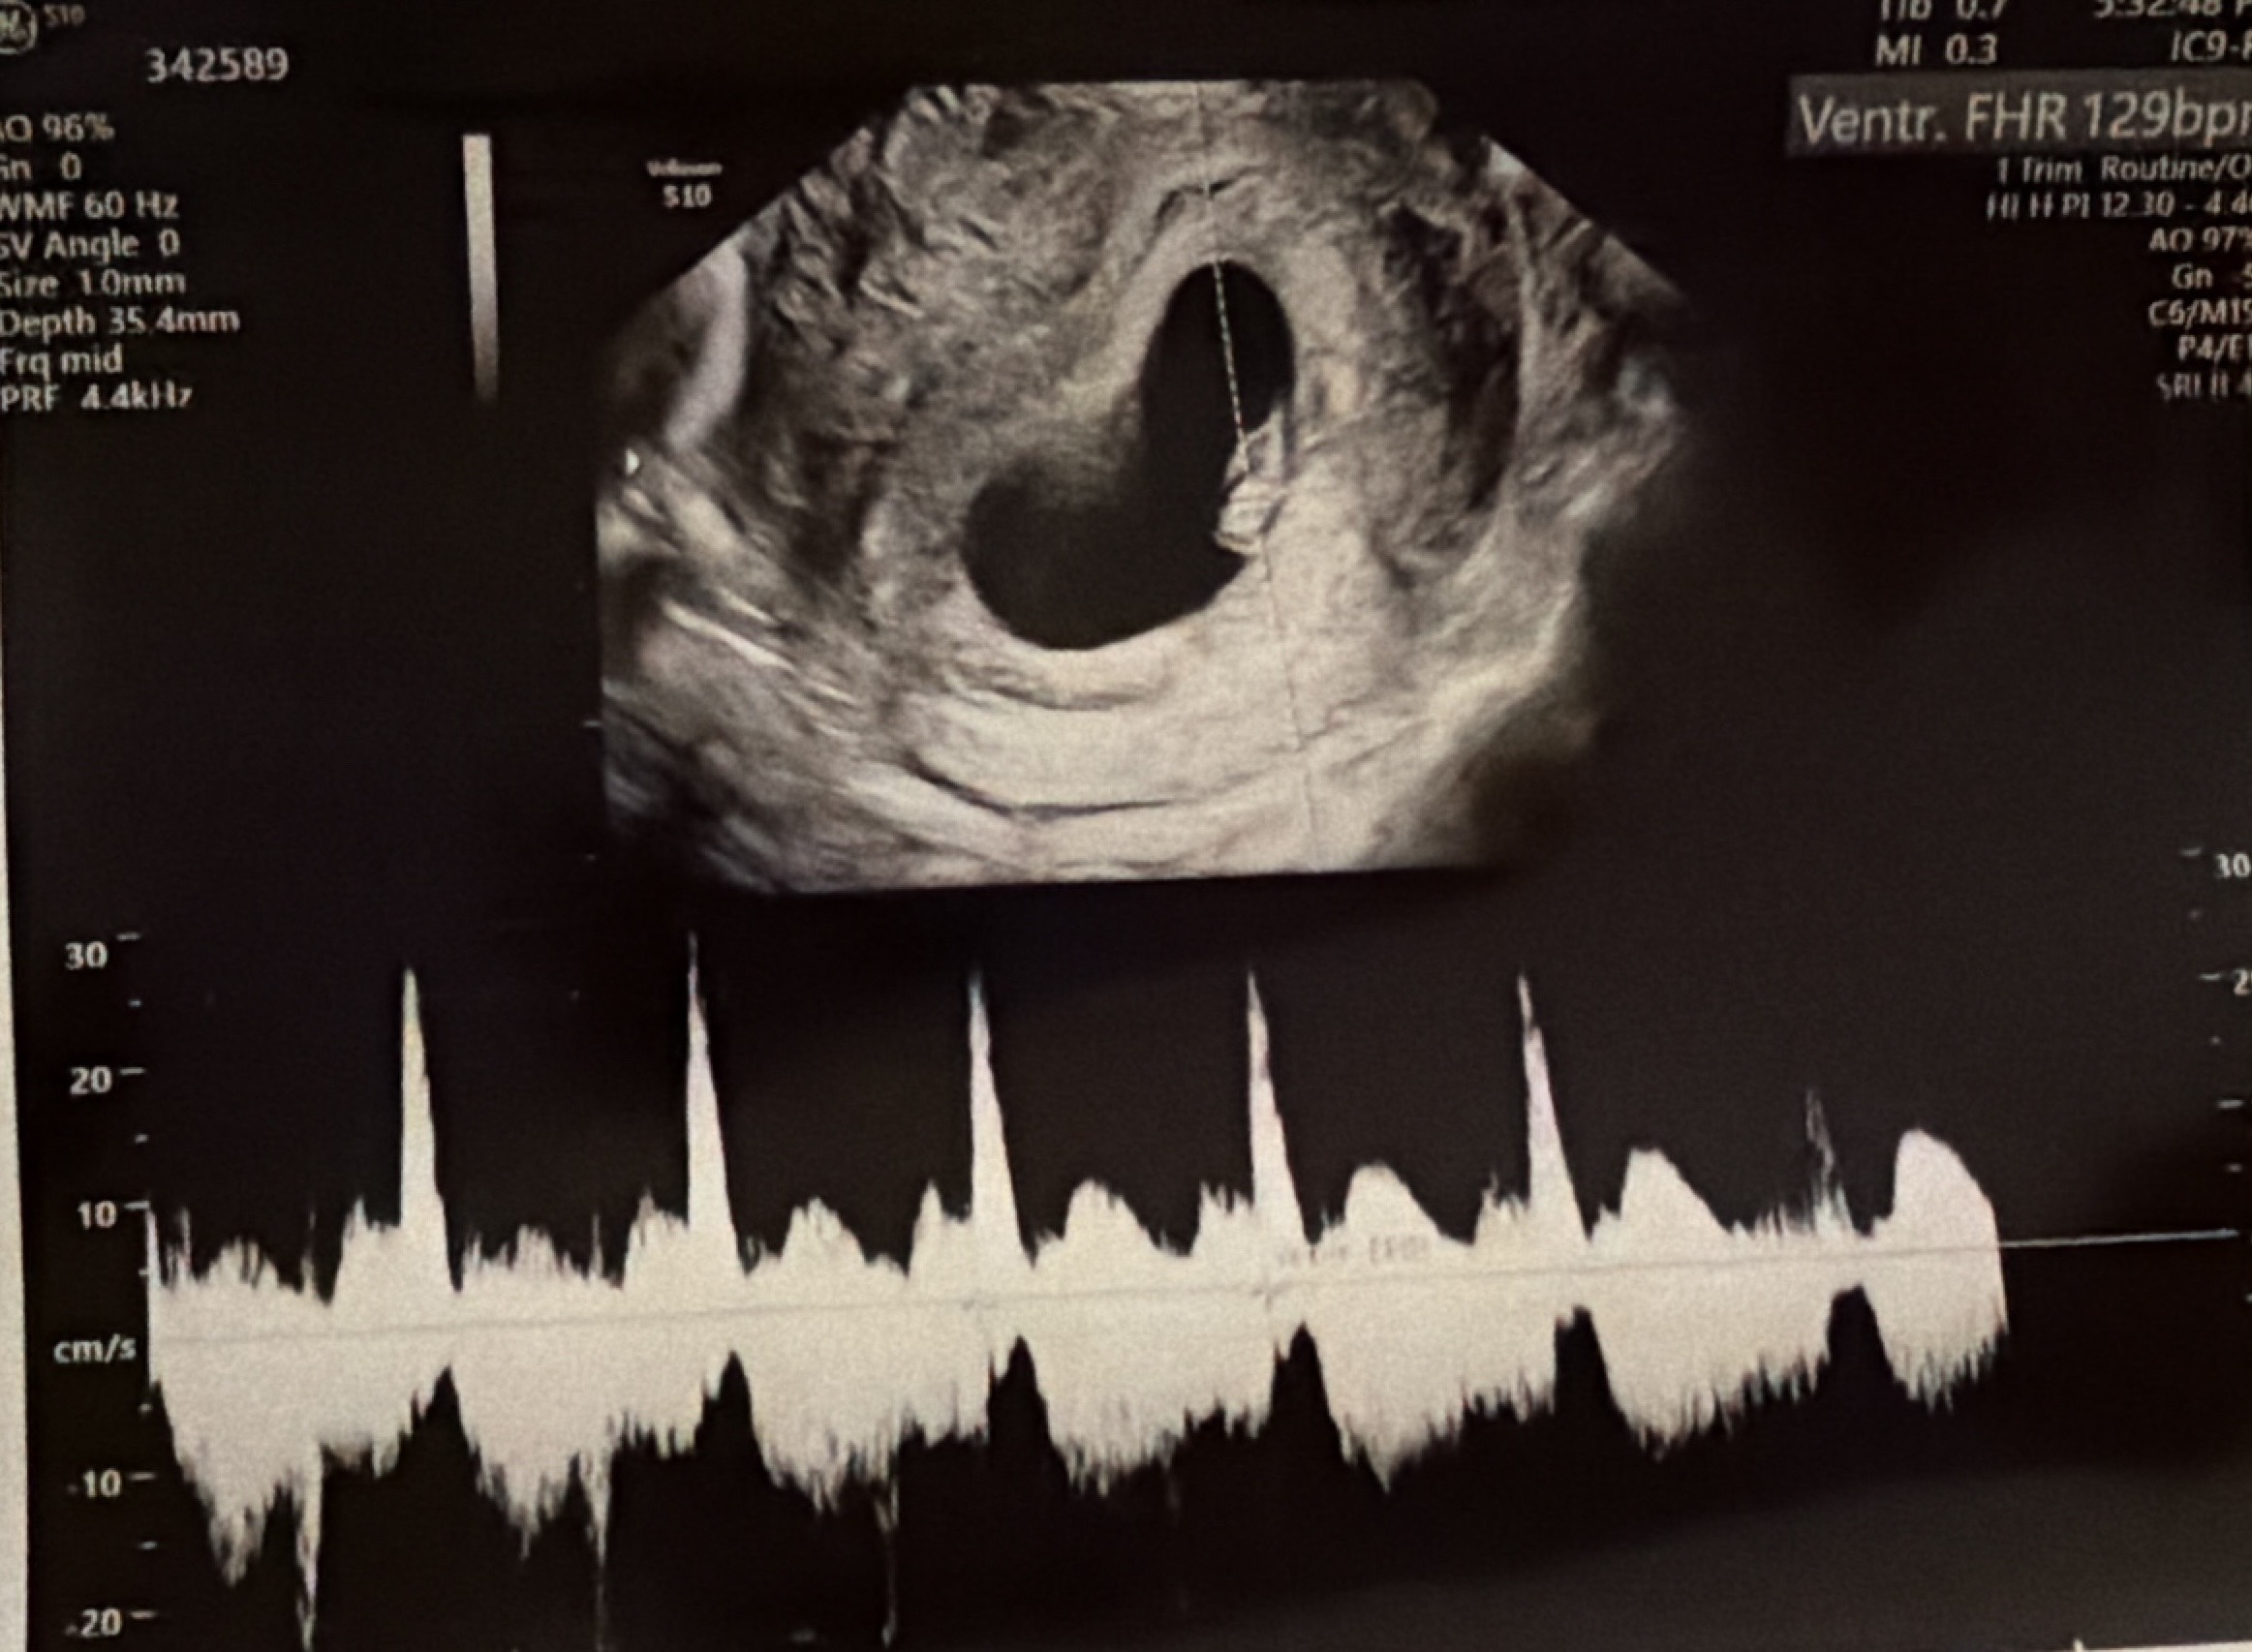

심장소리 듣고 왔어용ㅎㅎ

두근두근 심장소리 듣고 나니까 불안병이 쬐끔 사라졌어요 ㅎㅎㅎ 슬슬 입덧이 시작되는 것 같네용! 8월 맘들 파이팅입니다!🍀🤍